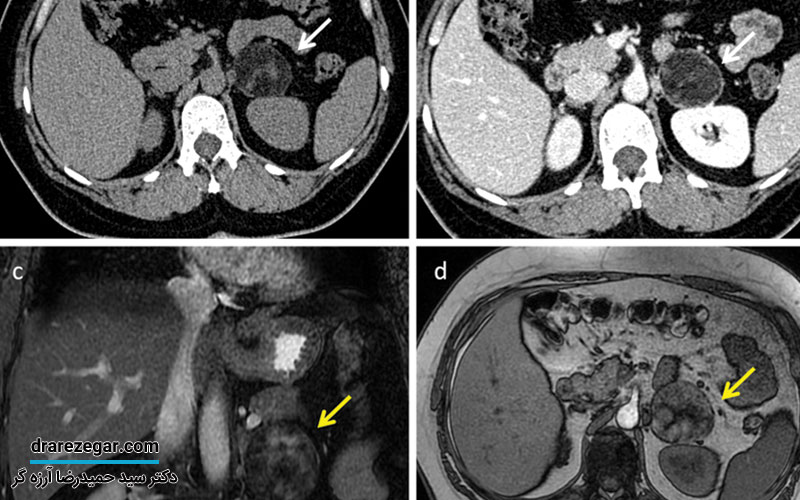

- تصویر برداری به روش های سی تی اسکن یا ام آر آی برای مشاهده اندازه تومور

- بیوپسی یا نمونه برداری از تومور برای شناخت دقیق نوع کیست آدرنال

روش های درمان سرطان آدرنال

امروزه با کشف روش های درمانی مختلف می توان موفقیت بیشتری در درمان و کنترل سرطان آدرنال به دست آورد. نوع روش درمانی پس از ارزیابی نتایج تست ها و تصویر برداری ها، مشخص می شود. در ادامه، به بررسی انواع روش های درمان سرطان آدرنال خواهم پرداخت.